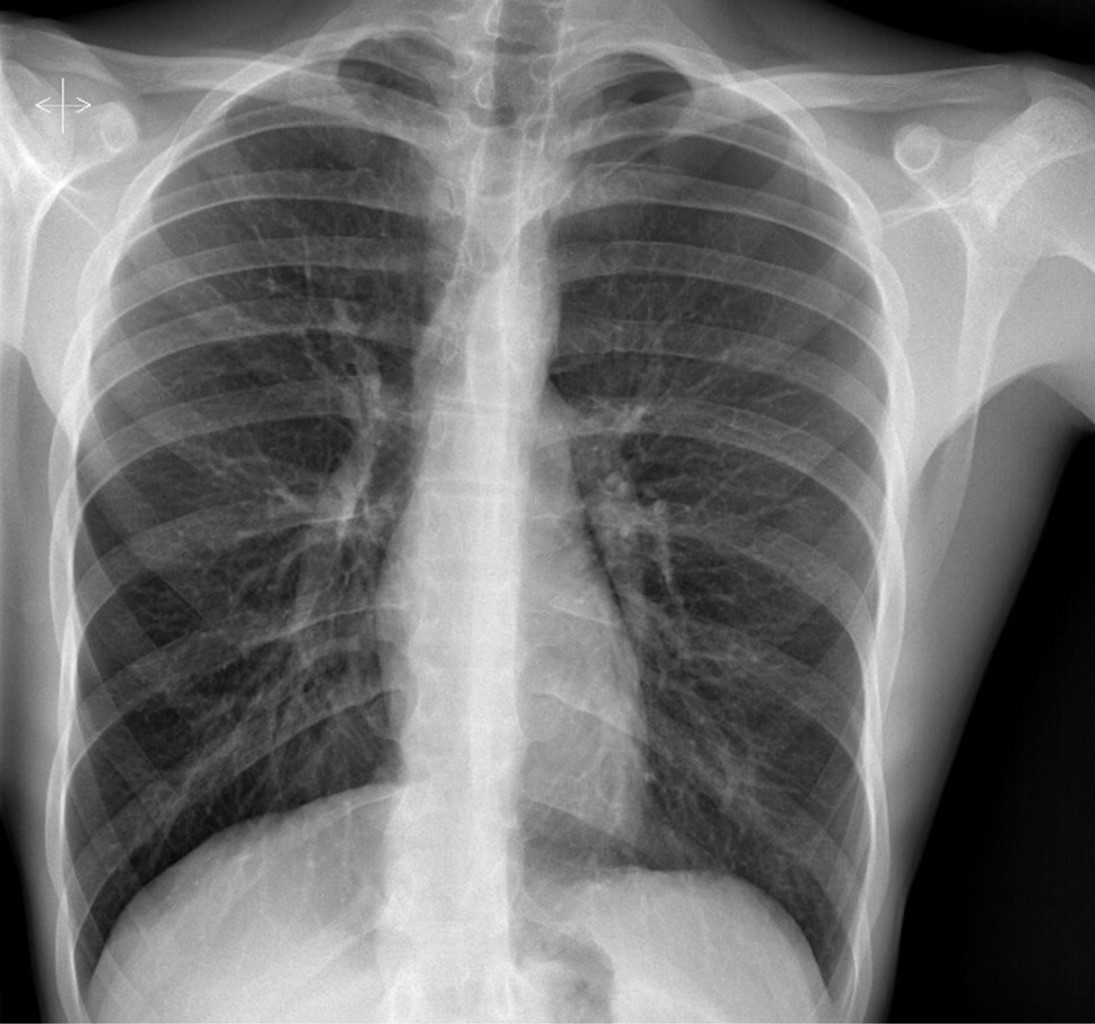

En tomografía axial vascular se evidencia sangrado activo, con probable dependencia de primera arteria intercostal izquierda. Mediante radiología intervencionista se realiza embolización con coil de 3 mm, aspirando 350 mL de líquido hemático, y posteriormente desaparece el derrame. Se envía a UCI para monitorización. A las 48 h, presenta empeoramiento clínico y radiológico, ya que aumentó el neumotórax al 65%, se detecta colapso pulmonar ipsilateral (Figura 3) y derrame pleural. Se decide realizar aspiración con jeringa a través de Pleurocath® obteniendo 70 mL drenaje hemático con componente aéreo. Se deja aspiración a 30 cmH2O, la cual se retiró tras la reexpansión pulmonar. Cabe señalar que permaneció hemodinámicamente estable en todo momento, sin necesidad de soporte hemodinámico ni transfusional. El paciente se egresó sin más eventualidades.

Figura 3